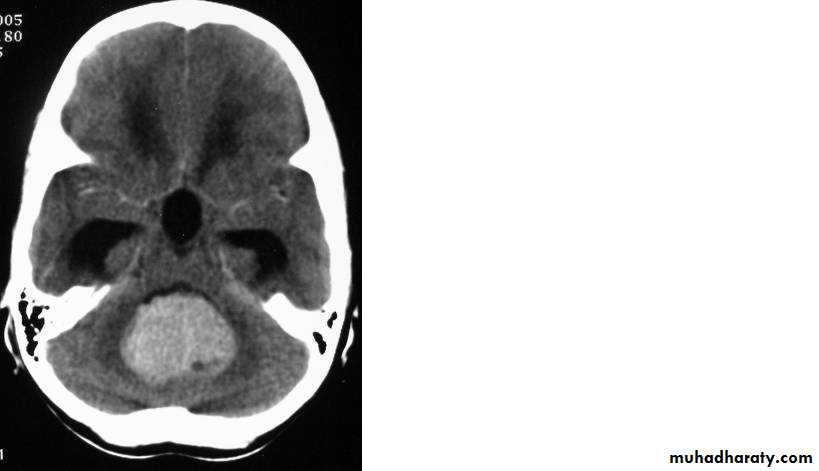

Malignant GliomaPre contrast CT

Neurosurgery

Malignant Glioma Post contrast CT